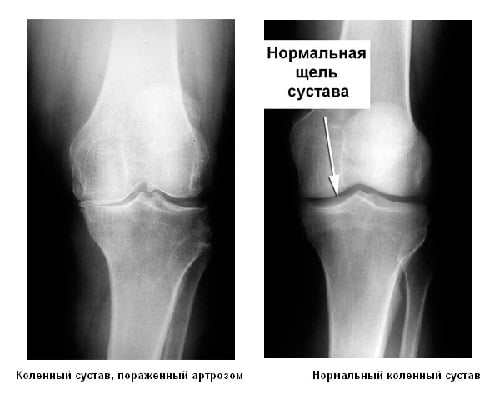

С помощью рентгенографии на этом этапе развития артроза поставить диагноз трудно, требуются дополнительные методы обследования.

Происходит сужение суставной щели, хрящевая ткань повреждается в значительной степени. На снимке, полученном в ходе рентгенографии, можно заметить разрастания кости. Острыми болями сопровождается любое движение, в котором принимает участие коленный сустав. В состоянии покоя неприятные ощущения проходят, но затем появляются снова. К болям добавляется характерный хруст при совершении сгибательно-разгибательных движений.

Местами хрящевая ткань истончается окончательно, образуются обнаженные участки кости. На рентгенограмме хорошо заметно большое количество остеофитов — отложений солей в полости сустава. Кроме того, там могут быть обнаружены свободные тела.